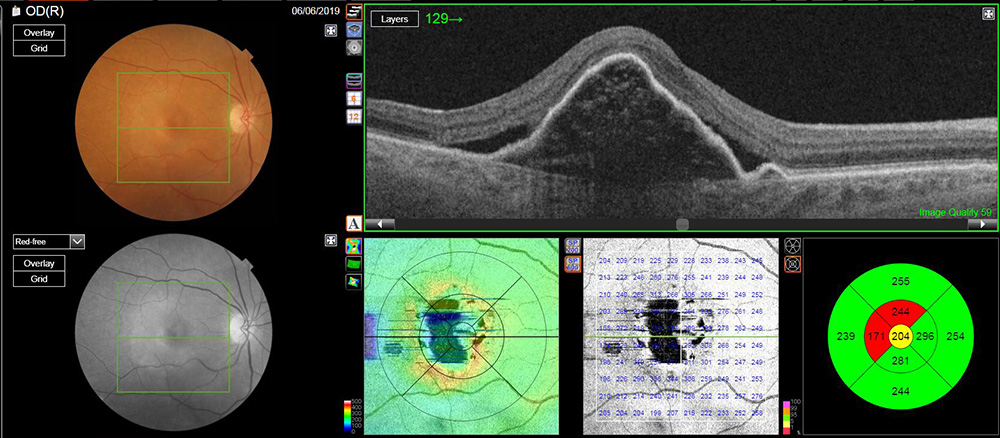

L’OCT (tomographie en cohérence optique) permet d’explorer en détail et en coupe les couches de tissu constituant la rétine, un peu comme un scanner. Cet examen permet notamment de mesurer l’épaisseur de la rétine afin de suivre son atrophie dans le temps, et d’observer les modifications structurelles des couches rétiniennes afin de caractériser les lésions maculaires. C’est un examen nécessaire pour distinguer les différentes formes de DMLA avant d’envisager un traitement ou une angiographie.

OCT d’une rétine normale

OCT montrant un décollement de l’épithélium pigmentaire et un décollement séreux rétinien typique d’une DMLA